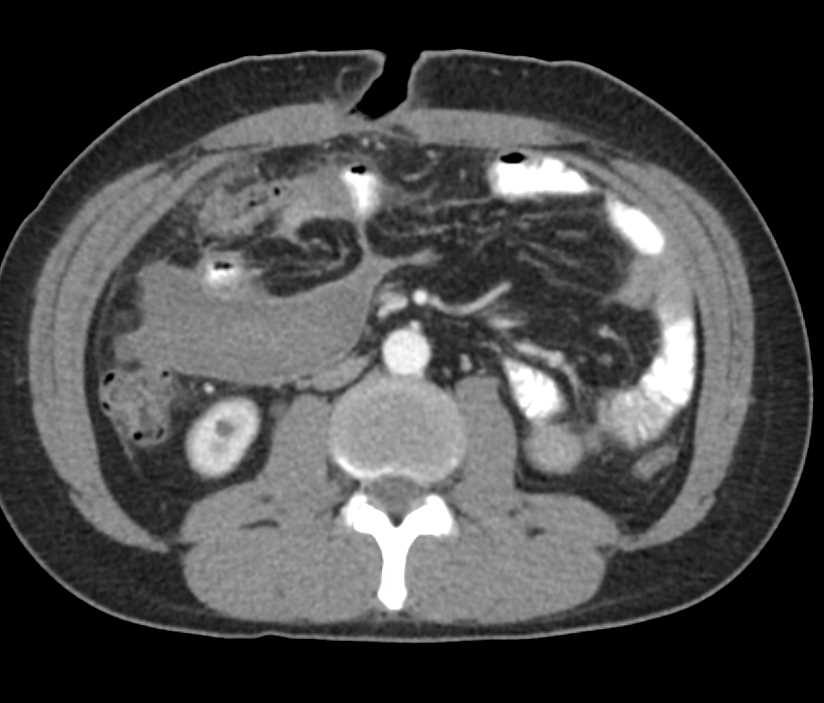

Superior Mesenteric Artery (SMA) Syndrome with Dilated Duodenum